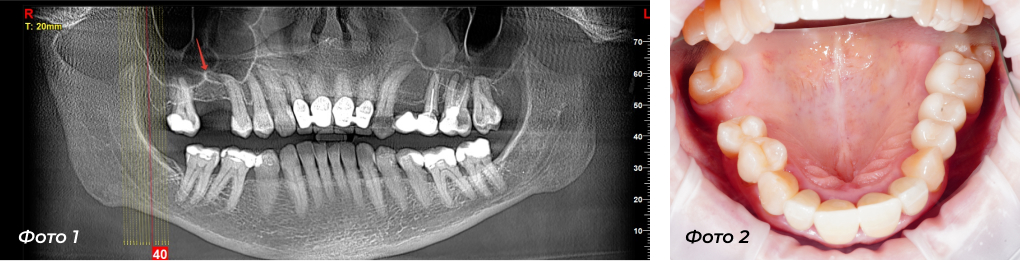

Проблема: пациентка обратилась с жалобами на отсутствие зуба на верхней челюсти справа (Фото 1 — стрелка указывает, где нет зуба). У пациентки недостаточный объем костной ткани по высоте, для установки импланта. Нужно проводить большую операцию по наращиванию костной ткани в этой области (открытый синус-лифтинг), то есть подсаживать костный материал в верхнечелюстную пазуху справа (в гайморову пазуху).

Фото 2 —  Отсутствует зуб наверху справа (вид в зеркало).

Лечение: У пациентки в области установки будущего импланта имеется ровно посередине выступающий костный гребень (септа — анатомия пазухи), чтобы не проводить большую операцию, было принято решение изготовить хирургический шаблон (3-Д модель) для установки импланта, чтобы при установке попасть ровно в костный выступ и получить дополнительную костную высоту.